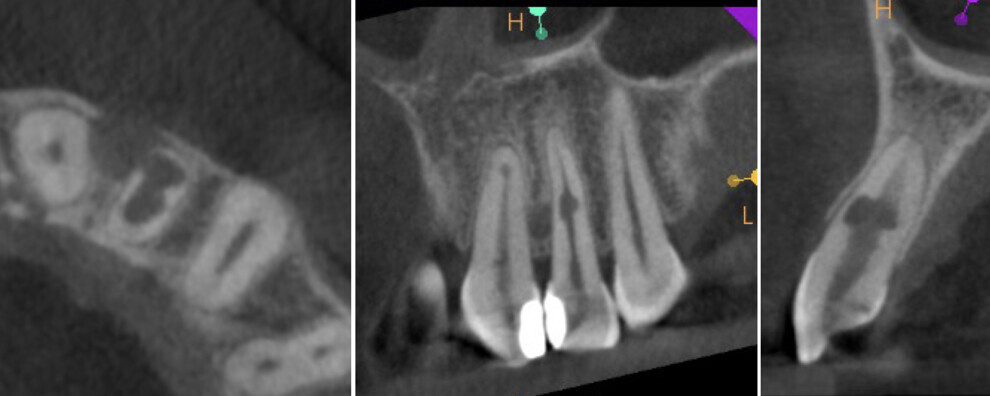

A 28-year-old patient was referred to the endodontic office after diagnosis of inflammatory IRR in the maxillary right central incisor on a periapical radiograph. A CBCT scan was taken to determine the prognosis and to plan the treatment (Figs. 8a-e). The 3D image revealed perforation of the labial wall of the root and destruction of the bundle bone surrounding the resorption cavity.

Fig. 8c: Radiograph (a) and CBCT scan (b–e) taken before the treatment, showing the root perforation and perforation of the cortical bone.

Recall appointments was performed after two (Figs. 16a & b) and four years (Figs. 17a & b). The radiographic examination showed the presence of bundle bone. The periodontal status was stable, and the tooth remained asymptomatic.

Figs. 16a & b: CBCT scan taken two years after the treatment.